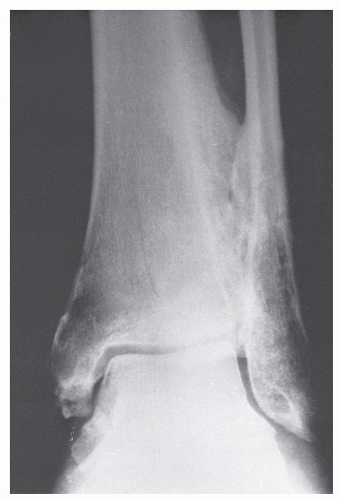

Рентгеновские снимки анкилоза суставов: Как это выглядит